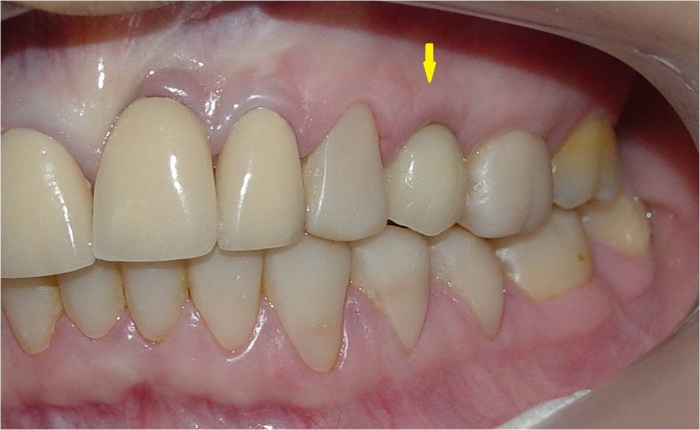

Dente de porcelana fixo sobre implante